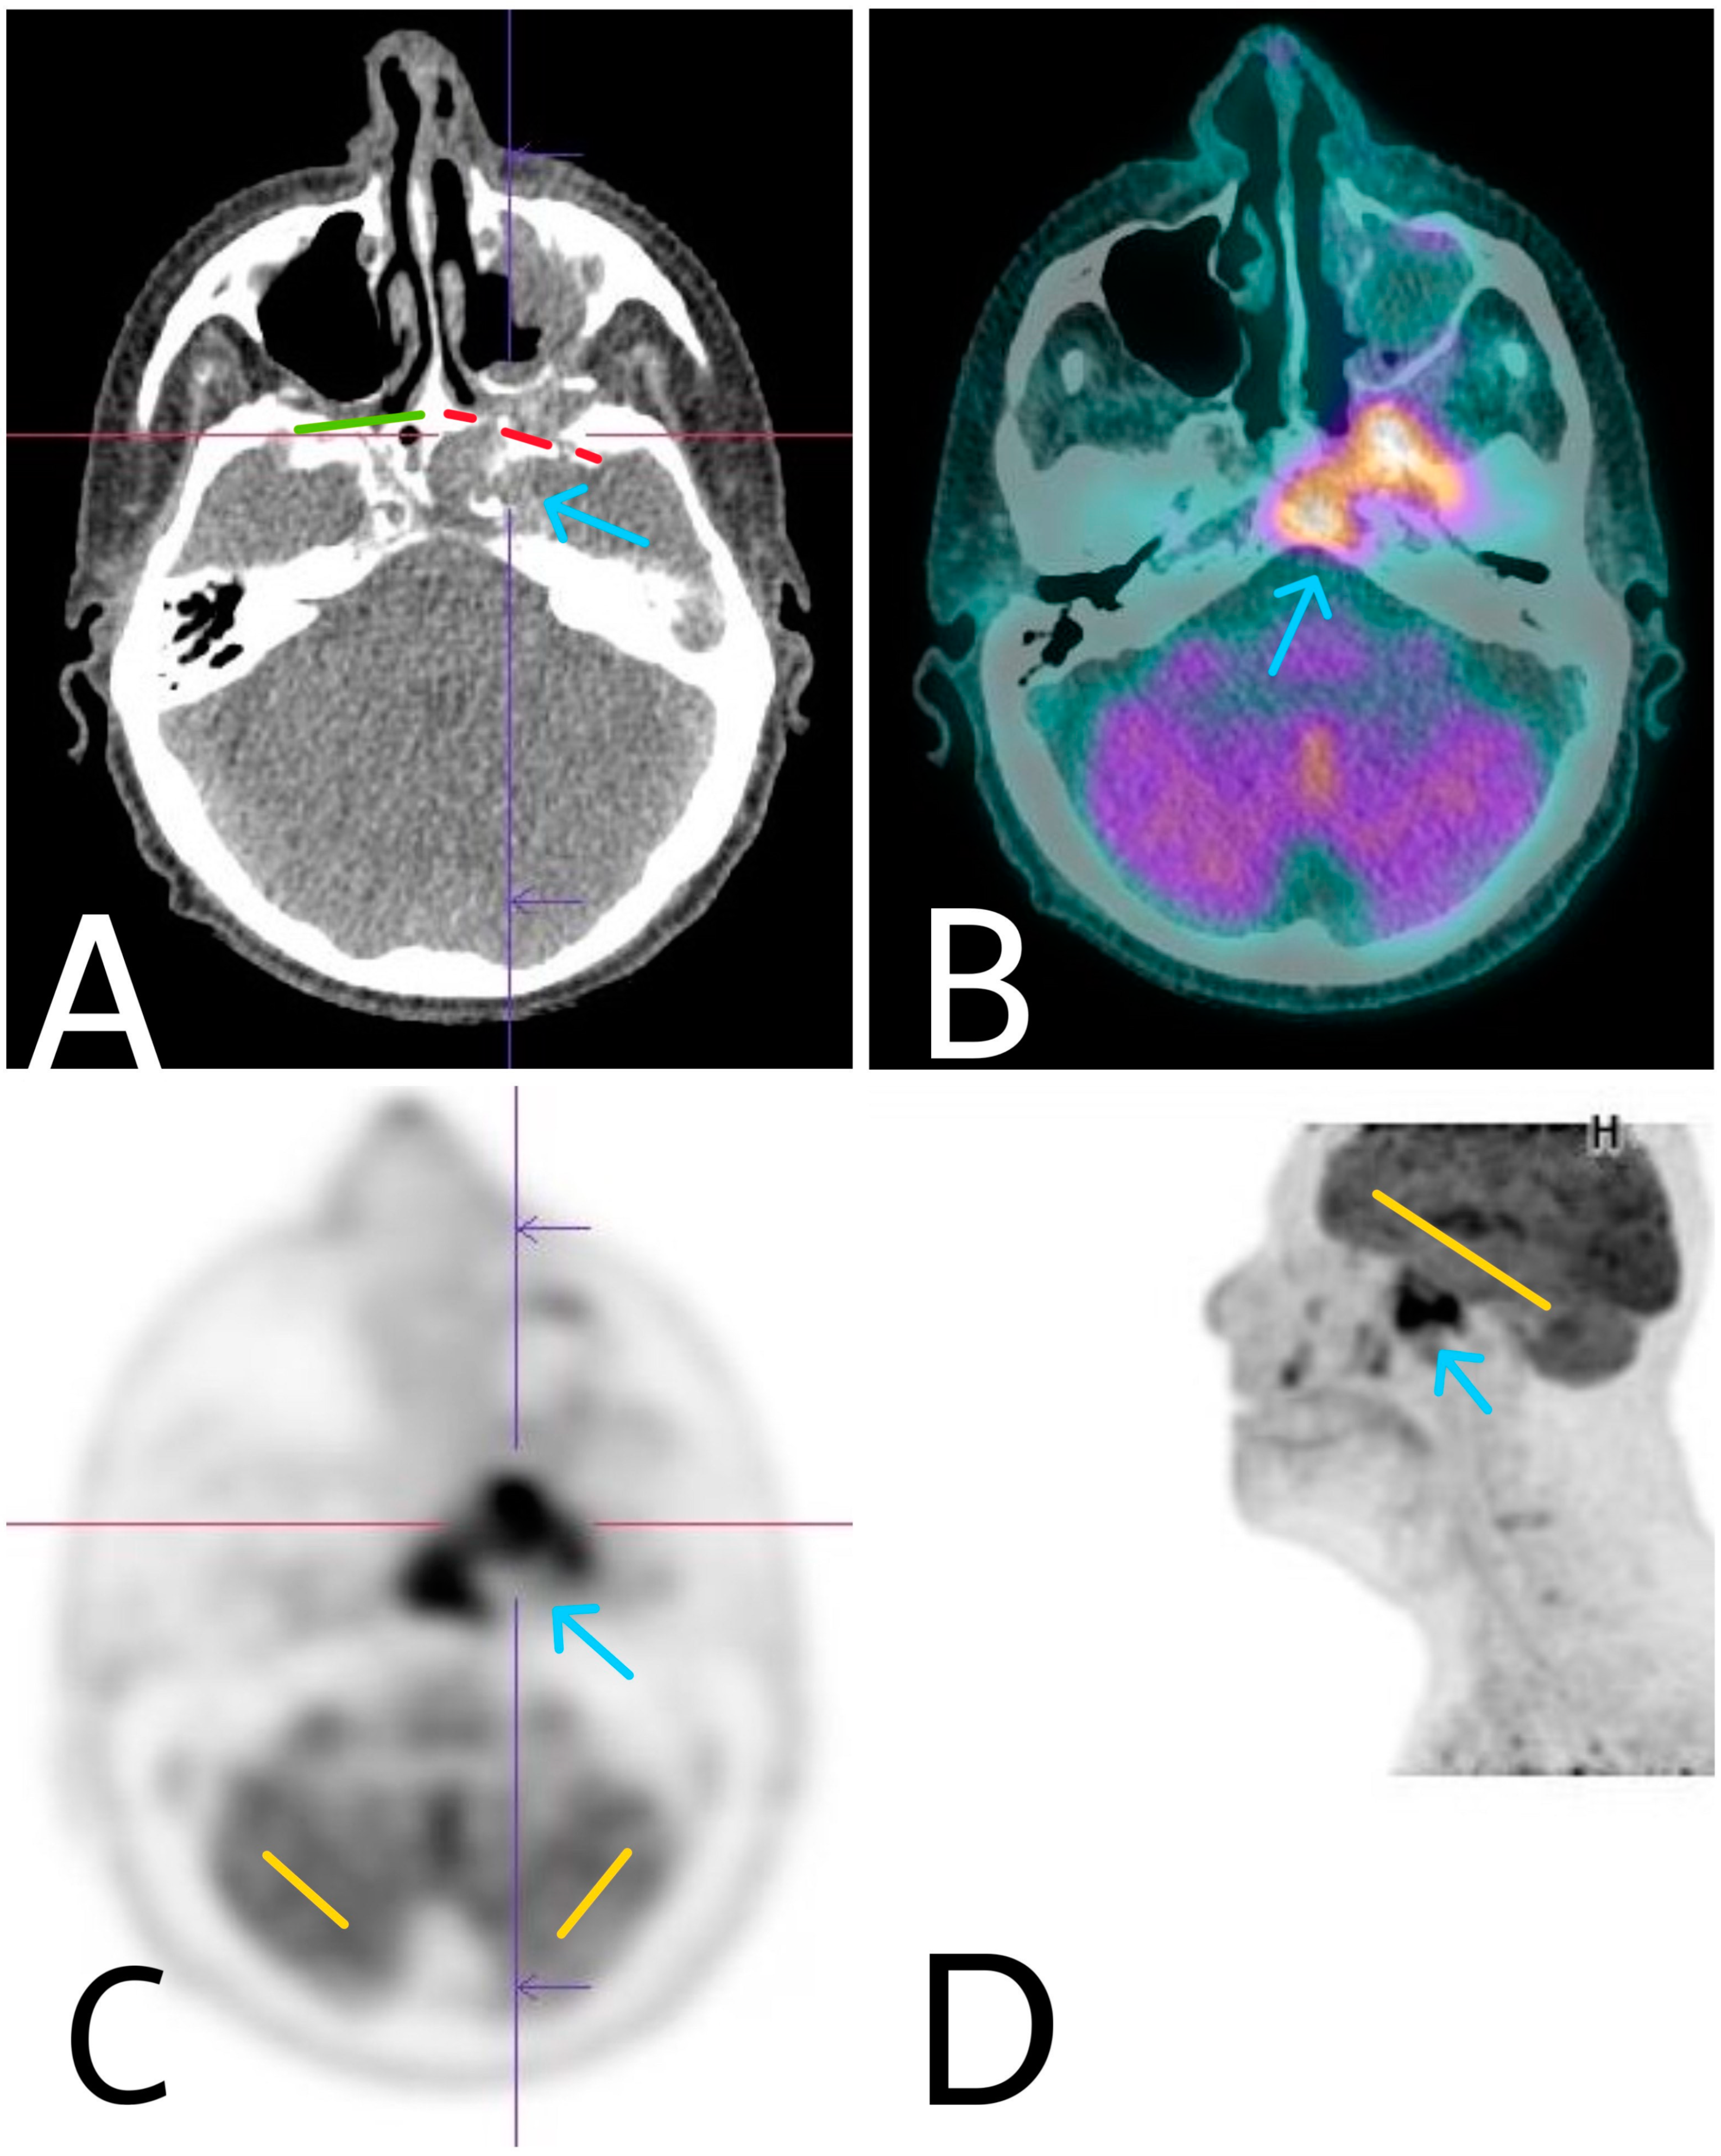

Figure 4. Axial CT (A), axial (C), and sagittal (D) FDG-PET and axial-fused PET-CT (B) image showing higher tumor metabolic activity, compared to the brains physiological one, extensive bone destruction, and extensive intracranial involvement by the primary pathological process. Green—intact bony borders of right orbit. Red—lytic bony borders of infiltrated left orbit. Yellow—normal brain metabolic activity.

For precision of the diagnosis, baseline staging of the process and planning of the therapeutic approach an FDG-PET/CT scan was required (Figure 4). FDG-PET/CT has the advantage of assessing morphologic as well as molecular information on cellular disease activity. It is also useful in detecting the primary lesion in tumors of unknown origin. In our case, the FDG-PET/CT did not reveal extension of the malign process outside the borders defined with the other imaging modalities, and the results of all imaging modalities were compatible.

The patient underwent an FDG-PET total body scan, MRI, echography of local lymph nodes and a multidisciplinary consultation to establish a therapeutic strategy. FDG-PET is an extremely useful and precious method in determining the systemic extension of the process and has a crucial role in the planning of the therapeutic approach if systemic metastases are detected. The method has a higher diagnostic performance compared to CT and MRI alone. Since the tumor process in our case was very invasive with distorted normal structures, the interpretation of CT and MRI scans was quite problematic. The FDG-PET/CT was extremely useful in defining the exact borders of the process and searching of distant metastases. There were no metastases and no involvement of the lymph nodes. Because of the large dimensions of the tumor process, its proximity to vital centers, and difficult surgery approach, a decision for performing radiotherapy was made. The patient received treatment doses of 12 Gy. Nagasawa et al. reported a 29.2-month average survival rate in patients with advanced intracranial SCC, who underwent radiotherapy with doses varying from 12 Gy to 15 Gy [8].